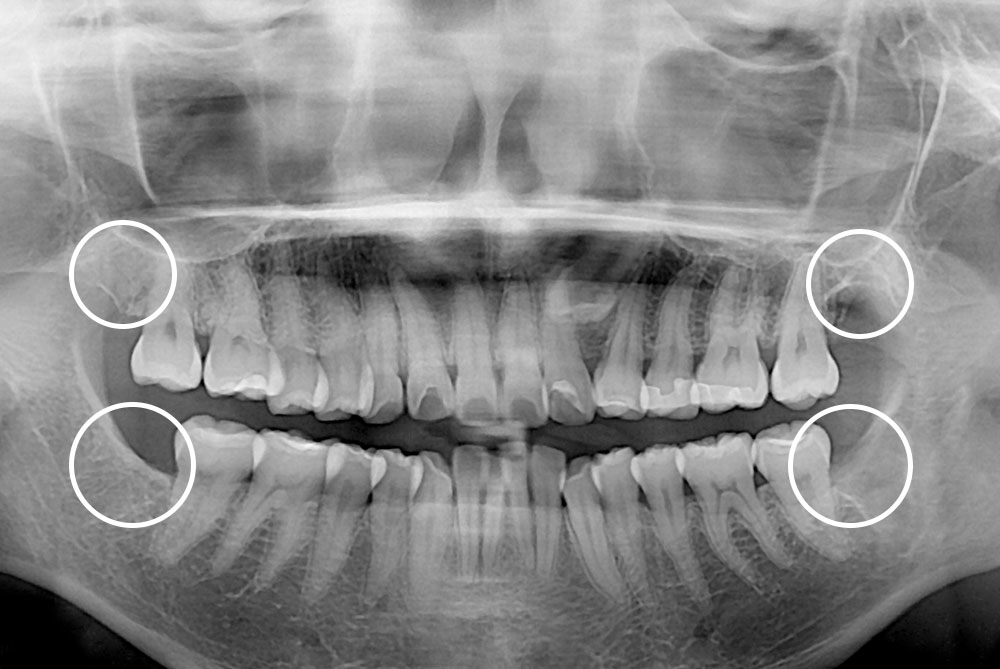

[사랑니] 매복 사랑니 발치

치료후 : 2020-07-07

세종치과는 구강악안면외과학 박사이신 원장님이 발치하는 치과입니다.